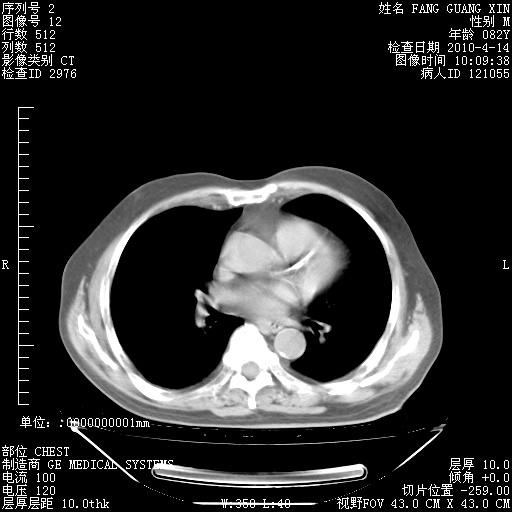

4月28日肺部CT——再次出现类似去年5月9日——透光度降低,(影像科认为)“间质性”改变。

4月28日肺部CT——再次出现类似去年5月9日——透光度降低,“间质性”改变。